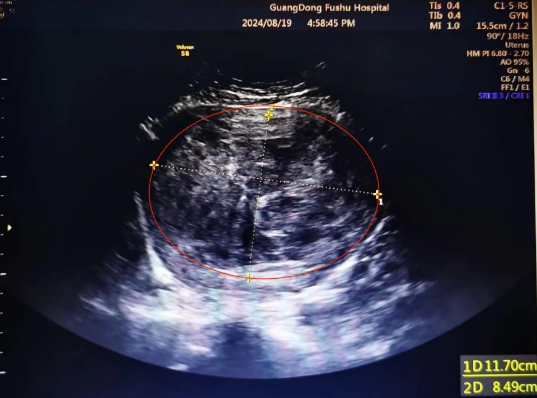

患者蔡女士,32岁,未婚无性生活,平时月经规律,自诉1个月前睡觉平躺时自己摸到下腹部有一个硬块,一开始单纯以为是自己吃太饱,可是大便后它还是存在。她十分担心,于是立刻来到广东医科大学附属医院陈惠娟医生的门诊就诊。体查发现蔡女士的腹部包块上界已经接近脐部,相当于妊娠4-5个月大小。妇科超声检查发现,蔡女士的子宫上长了一个117mm×85mm的肌瘤(见图1),必须进行手术剔除。看到这种结果,蔡女士和她母亲非常焦虑和担心。

(▲图1:妇科超声检查图,妇科超声室林景医生提供)